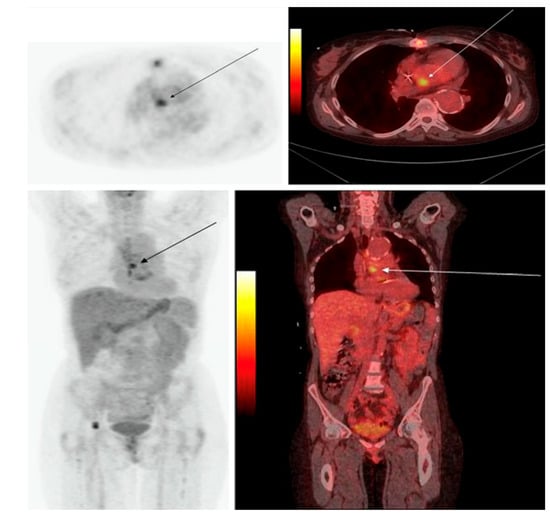

Several approaches toward the direct detection of bacteria have been put forward to develop specific radiotracers, including radiolabeled antibiotics, antibodies, antimicrobial or chemotactic peptides, and even bacteriophages [79,80]. For example, [68Ga]Ga-desferrioxamine-B ([68Ga]Ga-DFO-B) and [68Ga]Ga-pyoverdine PAO1 ([68Ga]Ga-PVD-PAO1) are radiolabeled siderophores which were developed in order to target bacterial transporters [81,82]. Peptides and amino acids which demonstrate accumulation in bacteria, such as D-[methyl-11C]methionine ([11C]D-Met) and [68Ga]Ga-NOTA/DOTA-UBI-29-41, have also been proposed as potential tracers used in PET imaging of infection [83,84,85]. In addition, [18F]FDS (Figure 5) and 6-[18F]-fluoromaltose have been investigated as alternative sugar-based radiotracers more specific to bacterial activity compared to [18F]FDG [86,87,88], which is taken up by bacterial and human cells alike. However, the results obtained so far have yet to demonstrate clinical utility. It is very likely that some of the positive results that have been reported with these bacterial agents are the result of hyperemia at the sites of bacterial infection; nonetheless, these results have been misunderstood as proof of the binding of these agents to bacteria.

Figure 5. [18F]FDS PET/CT imaging in patients with confirmed Enterobacterales infections. (a) Three-dimensional maximum intensity projection (MIP) from a patient with microbiologically confirmed Enterobacter aerogenes cellulitis of the left breast. Signal is also noted in the heart (blood pool), liver, kidneys, and the urinary bladder. (b) Three-dimensional MIP from a patient with MDR, extended spectrum beta-lactamase (ESBL)-producing E. coli osteomyelitis before and after inadequate treatment. Yellow arrows indicate site of infection (with permission from [88]).